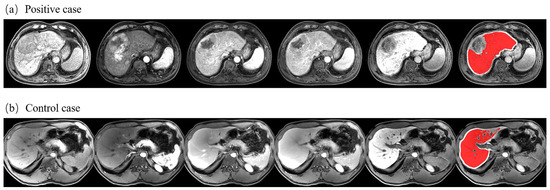

2.5.1. ROI Extraction